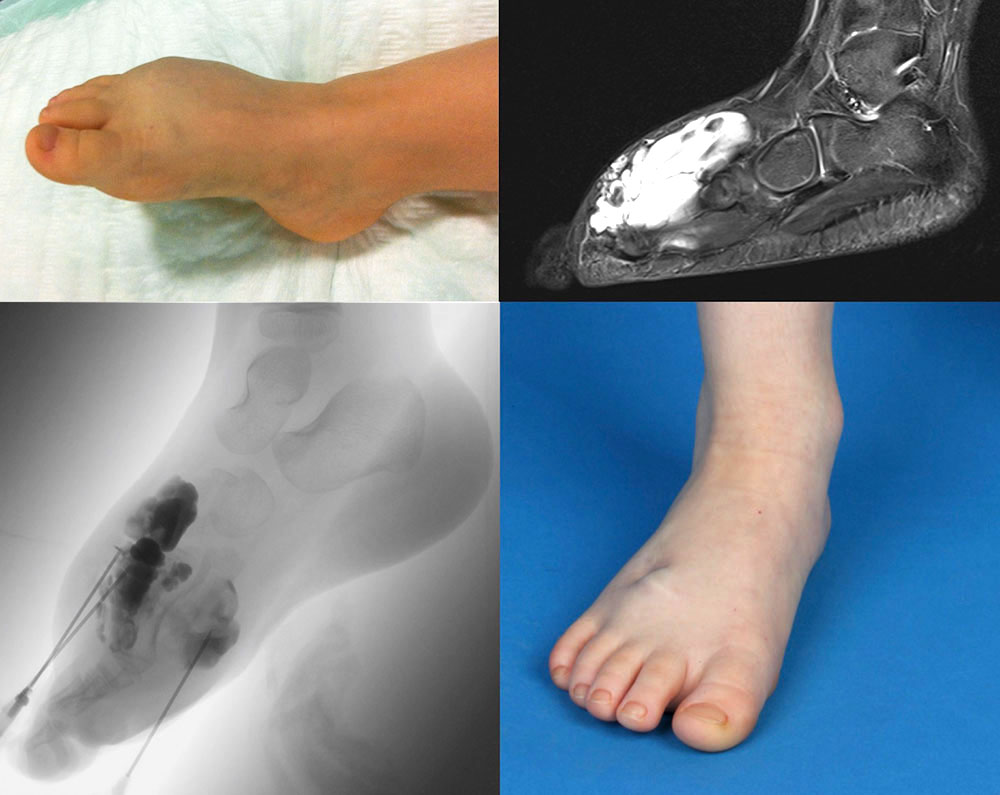

Because of their frequency, especially in venous malformations, acute thrombophlebitides are often  visualized incidentally in magnetic resonance imaging (MRI) as part of treatment planning, since this imaging is often performed in symptomatic patients. Thrombophlebitis per se is not an indication for MRI. The fresh thrombi present as hypointense (black) in T2-weighted images as compared to the very hyperintense (white) venous malformation. In T1-weighted imaging, they vary in signal intensity and may be isointense or slightly hyperintense to the blood in the surrounding venous malformation. As a result of the inflammatory reaction of the thrombophlebitis, there may be significant local enhancement after contrast administration; in fat-saturated T2-weighted imaging, surrounding edema can then also be visualized.

Thrombophlebitis is also depicted in direct phlebography or varicography (in the context of therapy). Intravascular thrombi present themselves as local non-contrasted areas within a vessel. Thrombophlebitis per se is not an indication for phlebography.